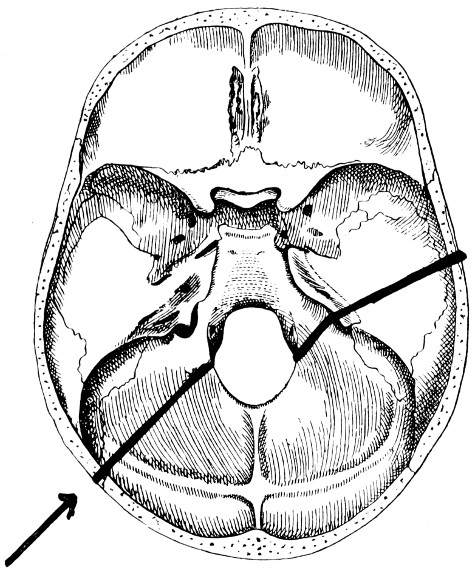

28. Illustrating the lines along which forces received on the vault are transmitted to the base 69

29 A and B. The base of the skull and the base as seen on transillumination 70, 71

30. Plan of the base of the skull 77

31. To illustrate the relation of basic fractures to cranial nerves 81

32-37. The lines pursued by basic fractures 83-8